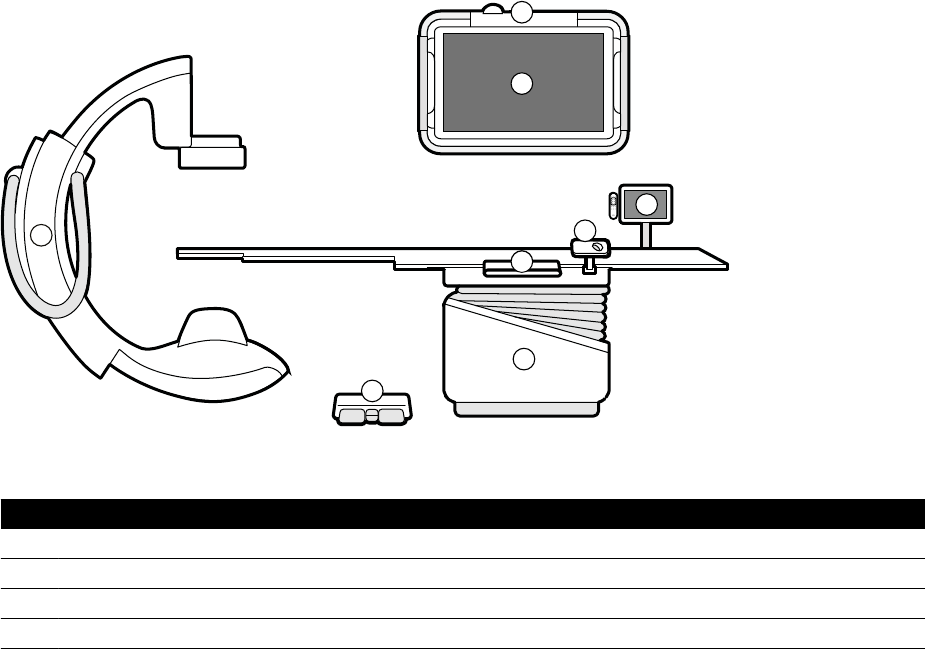

3.1 Wyposażenie w sali badań..................................................................................................... 26

3.1.1 Ramię C.................................................................................................................. 26

3.1.2 FlexVision (opcja)................................................................................................... 27

3.1.3 FlexMove (opcja)....................................................................................................27

3.1.4 Zapobieganie kolizji (BodyGuard).......................................................................... 28